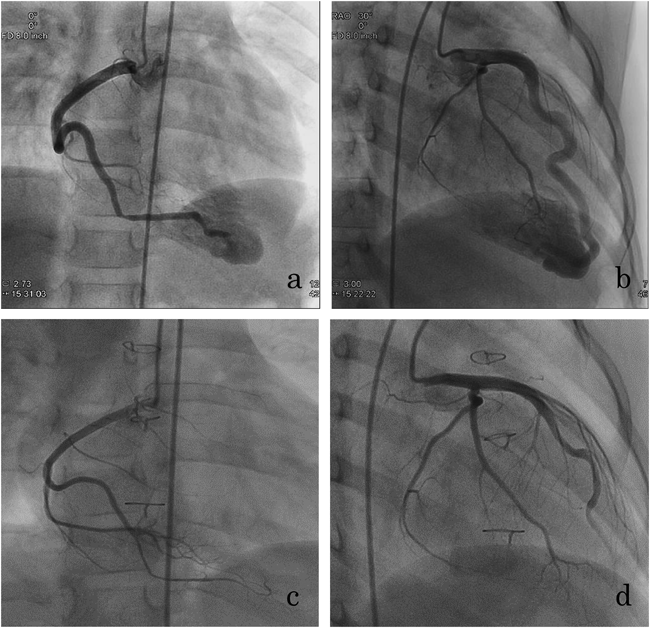

術後急性期からヘパリン(10単位/kg/日)を用い,抗凝固療法を開始.術翌日に一般病棟へ転棟.アスピリン,ワルファリンによる内服抗凝固療法開始.術後7日目に退院となった.術後6ヶ月での冠動脈造影では瘻孔の残存は認めず,拡張していた冠動脈も術前に比べ,縮小傾向を認めた(Fig. 3).

Pediatric Cardiology and Cardiac Surgery 32(3): 232-236 (2016)

Fig. 3 Preoperative (a, b) and 6-months postoperative (c, d) coronary angiography

a: RCA #1, 3.9 mm; #2, 2.6 mm. b: LAD #5, 5.0 mm; #6, 5.2 mm; #7, 4.2 mm. c: RCA #1, 2.7 mm; #2, 1.6 mm. d: LAD #5, 3.4 mm; #6, 3.2 mm; #7, 2.2 mm. a and b show right ventricle is contrasted, but c and d do not. RCA, right coronary artery; LAD, left anterior descending artery.